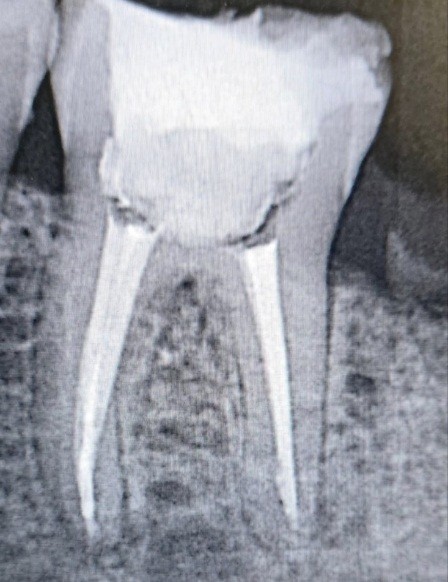

Например, при выполнении эндодонтического лечения с применением микроскопа врач может визуализировать пропущенные ранее корневые каналы, визуально оценить строение каналов, возможное наличие сломанных инструментов и пути их извления/прохождения, четко и по месту закрыть имеющуюся перфорацию корня/зуба, оценить весь необходимый объём очищения системы корневых каналов от остатков пульпы, предыдущих пломбировочных материалов и многое другое. Более того прекрасный обзор позволяет работать с минимальными иссечением здоровых тканей, но не упуская при этом даже самых крошечных очагов инфекции. Пломбировка корневых каналов при обзоре в микроскоп будет более объёмная - заполняющая все выступы и поднутрения в корневой системе. При восстановлении зуба композитной реставрацией с использованием микроскопа можно максимально точно оценить качество постановки пломбы и ее полировки - а это залог успеха и долголетия таких зубов.

2) перепломбировка корневых каналов под микроскопом; |